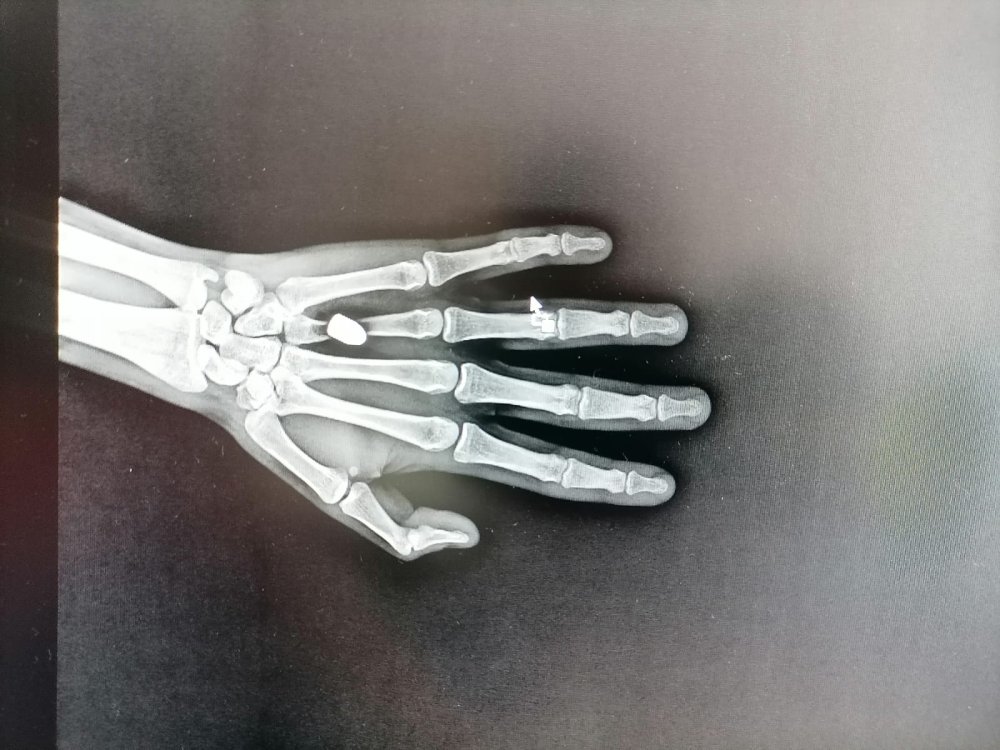

Trabzon'da en son 29 Temmuz'da annesiyle yolda yürürken göğsüne yorgun mermi isabet eden Alperen Yavuz, yaralandı. Ameliyatla kurşunun çıkarılıp, hayati tehlikeyi atlatan çocuğun, hastanedeki tedavisi sürüyor.